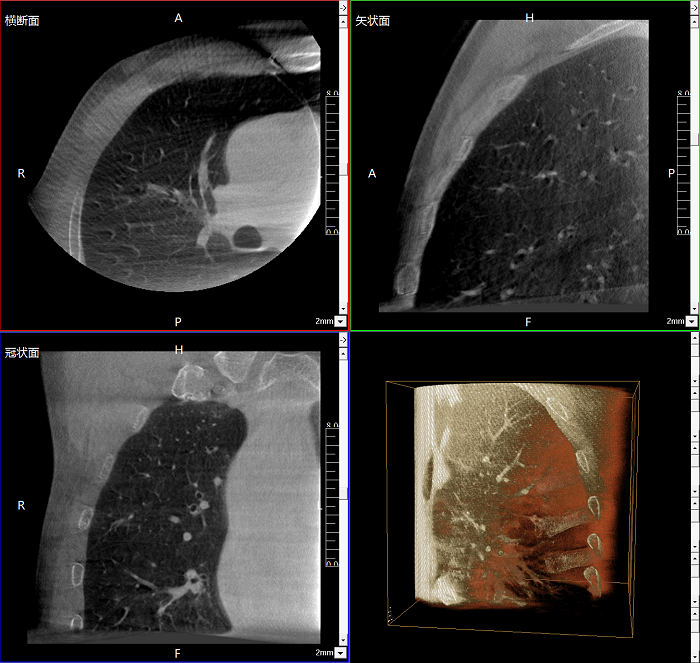

三維成像 全面觀察

任意視角、任意切面觀察

術(shù)中實(shí)時(shí)生成橫斷面、矢狀面、冠狀面及三維影像,可在任意切面、任意角度評(píng)估植入物和解剖結(jié)構(gòu)的相對(duì)位置。

術(shù)中CT檢查 減少翻修概率

通過(guò)術(shù)中三維影像的檢查,可以立即發(fā)現(xiàn)植入物的錯(cuò)位,減少不必要的第二次手術(shù),減少并發(fā)癥概率以及感染風(fēng)險(xiǎn)。